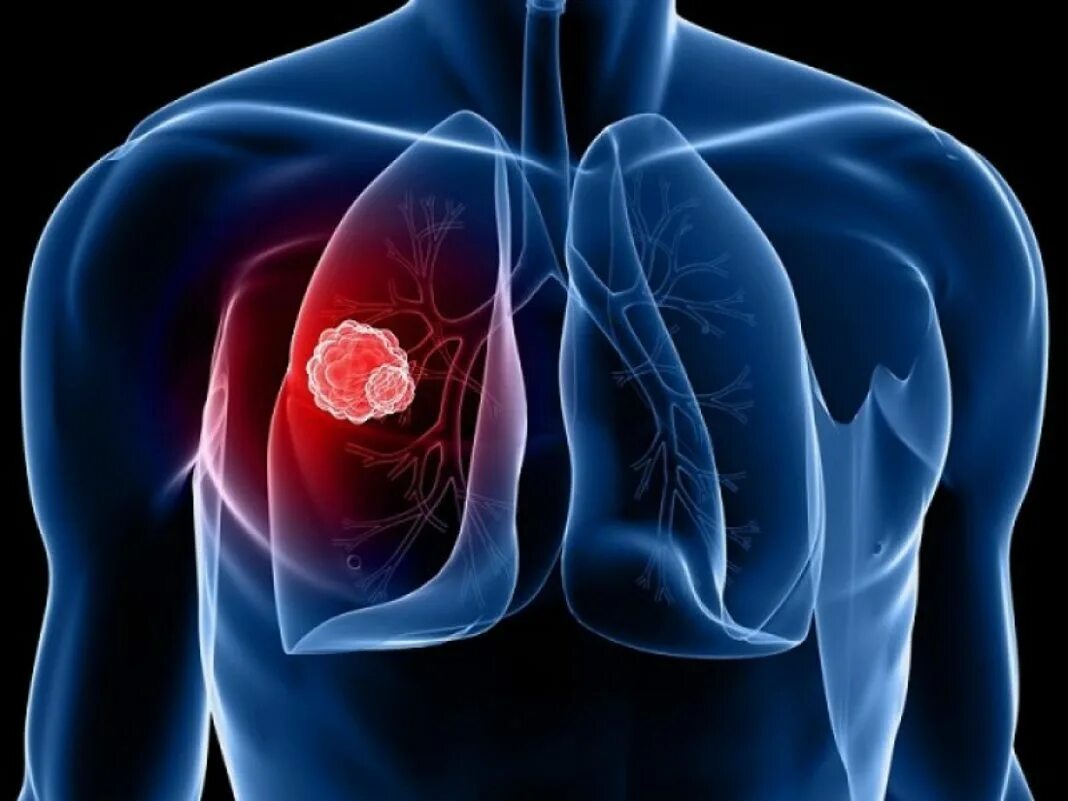

Онко легкие